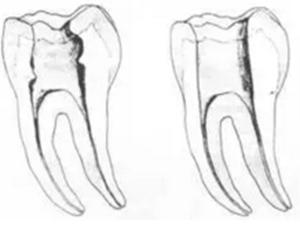

二、根管預(yù)備后形態(tài)

牙體缺損的修復(fù)需要將剩余牙體組織制備成一定形態(tài),以利修復(fù)體的良好固位。根管充填為了致密封閉根管系統(tǒng)也需要良好的根管預(yù)備后形態(tài)。

常規(guī)概念的根管預(yù)備后形態(tài)有:

1. 便宜形態(tài)

便宜形態(tài)是自切端或咬頜面朝向根尖的直線開擴(kuò)尖錐形態(tài),減少污染物推出根尖孔,方便沖洗、根管充填和側(cè)壁施壓。

2. 保持形態(tài)

保持形態(tài)是根尖狹窄部內(nèi) 1 — 2mm 的一段距離,由擴(kuò)大器回轉(zhuǎn)切割而不貼根管壁提拉切割制成,是擴(kuò)大器的原始形態(tài)(近似平行)。在測試主牙膠尖時給測試者有一個牽引抵抗 (tugback) 的感覺。

3. 抵抗形態(tài)

抵抗形態(tài)是根管預(yù)備的根尖形態(tài),它是由擴(kuò)大器或根管銼尖端 75 度角自然切割而成。其目的是防止根管充填材超出根尖孔,并且使根尖封閉更加嚴(yán)密。